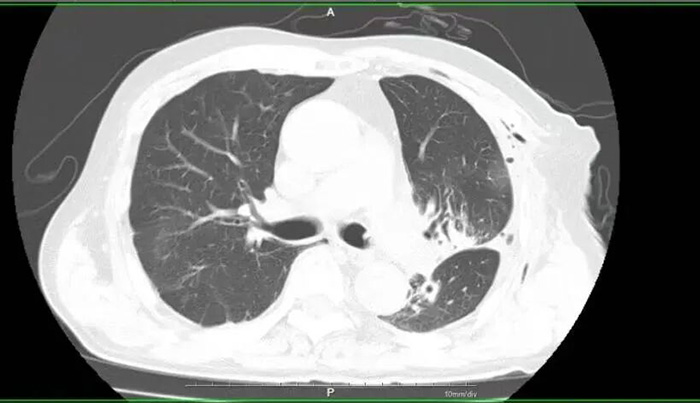

▲术后复查CT 手术成功只是第一步,术后康复同样关键。作为快速康复外科示范病房,胸外科团队并没有就此止步,而是结合李大爷的年龄和既往病史,从饮食调理、适度运动、肺功能锻炼到并发症预防,为他定制了全方位的个性化术后康复方案。在医护人员的精心照料和李大爷的积极配合下,术后仅3天,他就顺利拔管,可自主活动、正常进食,最终顺利出院,出院时李大爷握着医护人员的手,连连称赞:“多亏了你们的好技术,让我少受罪、花少钱,还能这么快康复!”术后病理结果也证实,李大爷所患的是浸润性腺癌,此次精准切除已达到根治效果。